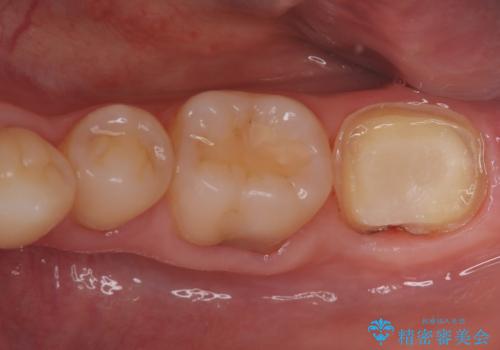

- 患者様は、他院で根管治療を受けたものの、違和感が続くため「しっかりとした治療を受けたい」とのご希望で来院されました。診査の結果、根管内の感染が完全に除去されておらず、根の先に炎症が残っている状態でした。そこで、精密根管治療を行い、感染源を徹底的に除去する計画を立てました。マイクロスコープを使用し、4回の治療で根の内部を清潔にし、最終的にしっかりと密封することで、長期的な安定を目指しました。

治療は、まず根管内の古い充填材を取り除き、感染部分を徹底的に洗浄・消毒することから始めました。ラバーダム防湿を使用し、治療中の細菌感染を防ぎながら、マイクロスコープを用いて根管の細部まで確認しながら処置を進めました。4回の治療で感染の除去と根管の封鎖を行い、最終的に土台を立てて被せ物の準備を整えました。患者様からは「違和感がなくなり、噛んでも痛くない」と喜びの声をいただきました。